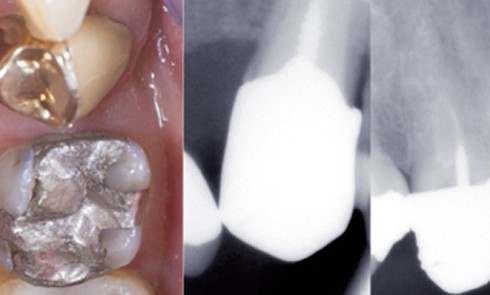

Article réservé à nos abonnés La dépose des éléments prothétiques coronaires et intra-canalaires

Tout élément prothétique a une durée de vie limitée, et ce, malgré tous les moyens mis en œuvre lors de...

Le retraitement endodontique implique une évaluation préopératoire rigoureuse afin de comprendre les causes de l’échec du traitement initial et de...